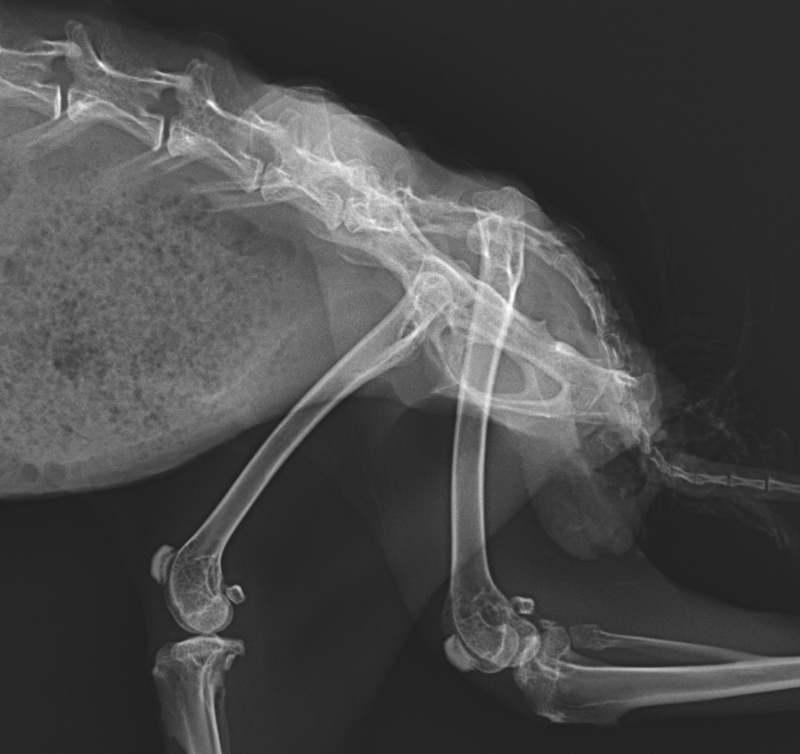

Figure 2 from Feline hip dysplasia Semantic Scholar How To Fix A Dislocated Hip On A Cat Treating a dislocated hip quickly can help reduce chronic, degenerative arthritis from developing in the cat. For example, cats with hip dislocations often need surgery to repair their joint. Hip dislocation, from hip dysplasia or from injury, along with a luxating patella (sliding knee cap) are among the most common. If your cat has undergone a surgery to correct its. How To Fix A Dislocated Hip On A Cat.